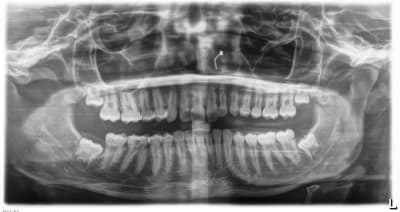

Et pour ceux qui me demandaient la pano de l'année précédente, exactement 1 an et 3 mois précédemment, la voici.

Vous pourrez comparer l'évolution rapide de la tumeur bénigne qui a refoulé les structures en les soufflant.

01/10/2025 à 07h31

Tout est allé très vite pour elle.

Même l’edification radiculaire des dents de sagesse en l’espace d’une année est surprenante 🤔

Moi ce qui m'impressionne c'est le déplacement de la 38.